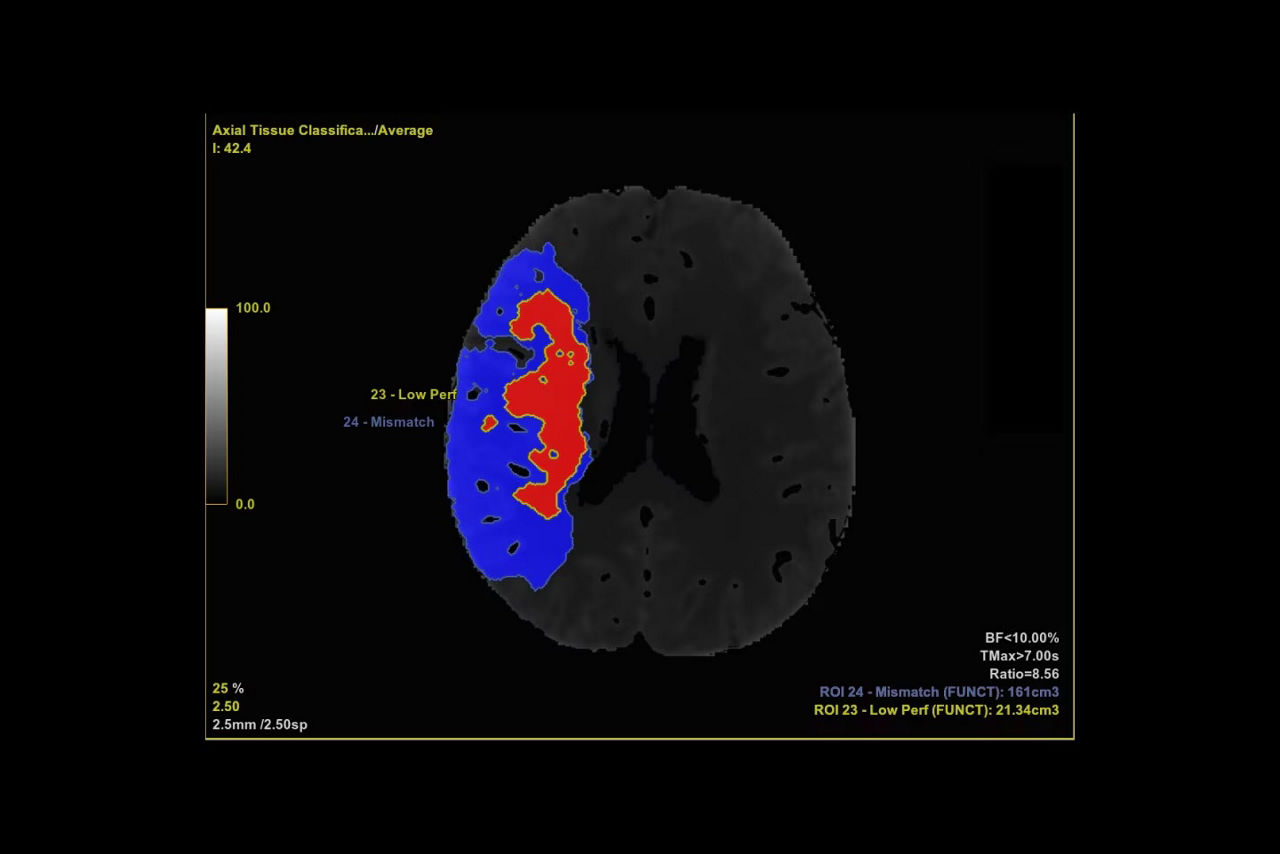

Perfusion maps and tissue classification

• Tissue Classification map segmented from absolute or relative values, customizable thresholds and user selectable input maps

• Mismatch volume and ratio calculated from the Modified Perfusion region and the Low Perfusion region